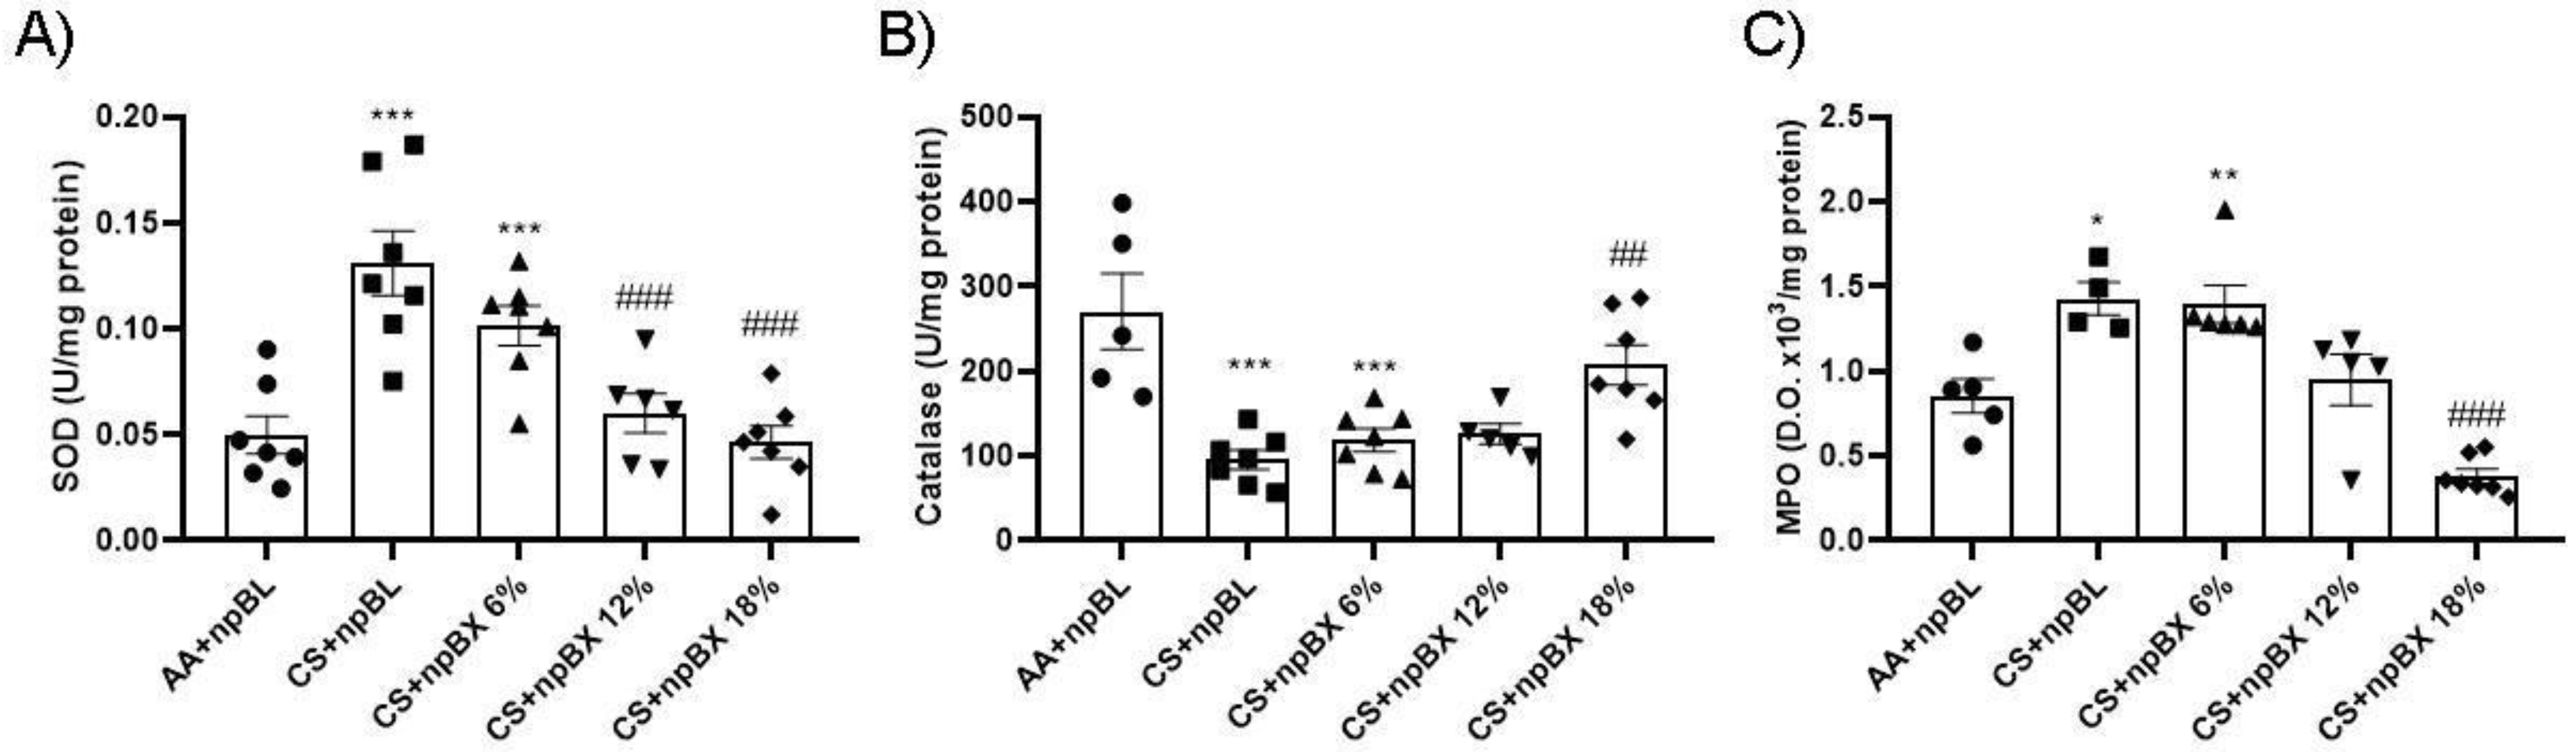

3.3.3. npBX Prevents Redox Imbalance Induced by CS Exposure in Mouse Lungs